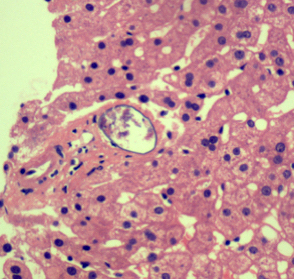

Microscopic (histologic) description

- Ova are mainly seen in the loose submucosa of large intestine, usually with formation of granulomas and infiltration by eosinophils and inflammatory cells

- Later the muscularis mucosa becomes involved and the overlying mucosa shows small superficial ulcers

- Fibrosis develops in chronic stage, when only calcified eggs are seen

Microscopic (histologic) images

Contributed by Nalini Bansal Gupta, M.D., Lisa Cerilli, M.D. and @zaalruwai83 on Twitter